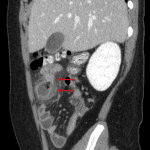

- Dilated blind-ending structure arising from the distal ileum with surrounding fat stranding

- Meckel diverticulitis

Findings consistent with Meckel diverticulitis. Appendix is normal.